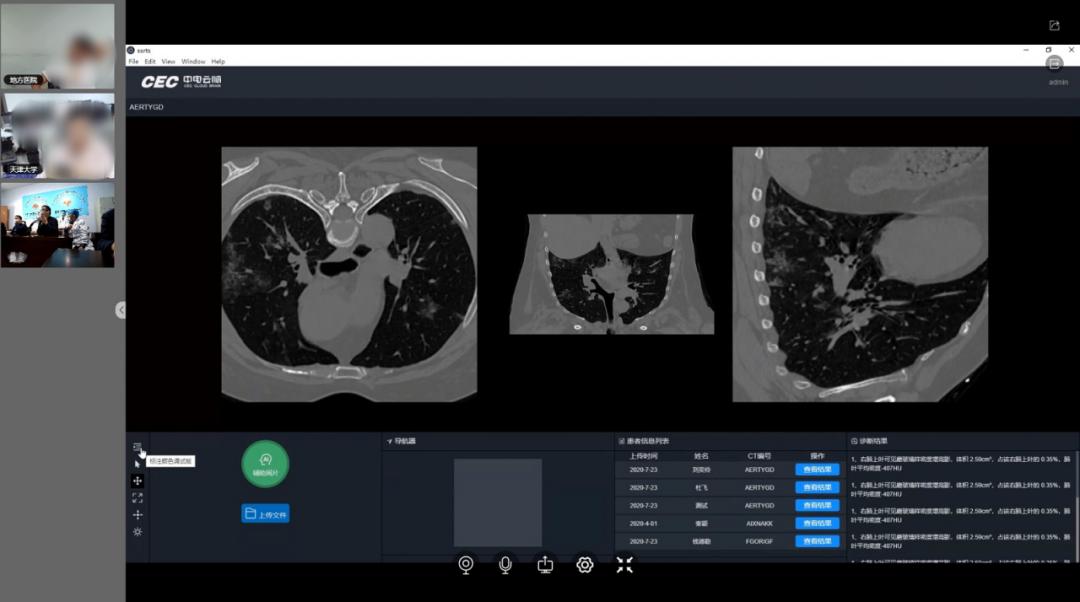

天津大学针对此问题,协同中电云脑(天津)科技有限公司,充分发挥健康医疗大数据国家队在数据赋能方面的优势,联合开发了天津大学远程医教会诊平台。平台利用深度学习和计算机视觉,基于医学影像数据实现关键脏器的多部位与多任务分割,实现特征计算与智能辅助诊断,为临床影像诊断提供更丰富的决策信息,客观上能帮助医生降低误诊、漏诊率。

不仅如此,基于平台还将集成已有的电子病历、影像资料等,经过数据脱敏、技术处理后对县内医院进行有针对性地共享。县内医生可通过平台快速检索与患者类似症状的病历信息,在参考诊断结果、用药信息等内容的基础上,为患者提供更为准确、迅速地治疗,从而进一步提高县内医院的医疗服务水平。